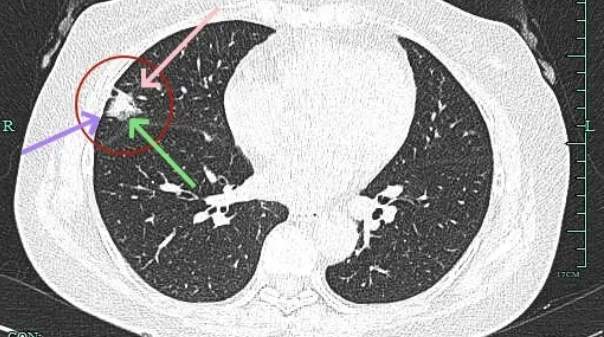

病灶出现,磨玻璃密度,轮廓较清,此层示见显著实性成分。

边缘不平有毛刺,实性成分开始出现,外周仍是磨玻璃密度的。血管与之关系密切。